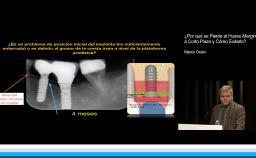

Esta presentación nos orienta y guía en la utilización de la herramienta SAC (simple, avanzado y complejo) de las Guías de Tratamiento ITI. Son dos casos clínicos complejos que son utilizados como soporte ilustrativo en el desarrollo de la charla.

- valorar la suma importancia del manejo de la posición tridimensional en los implantes a colocar

- entender que losriesgos estéticos y protéticos se pueden disminuir de manera drástica si modificamos el terreno previamente (tejidos duros y tejidos blandos ) cuando esto es necesario, facilitando la colocación de los implantes, simplificando lo complejo